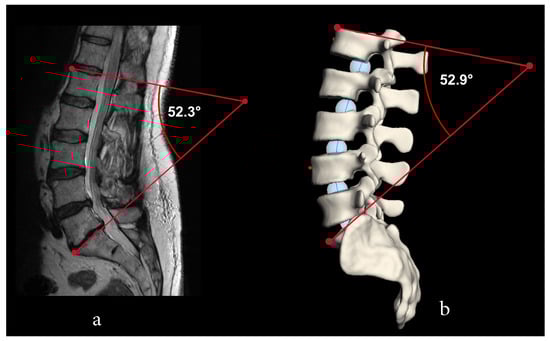

| 52.3 | 52.8 | 57.1 | 54.1 | 2.6 | |

| 52.9 | 52.8 | 52.7 | 52.8 | 0.3 |